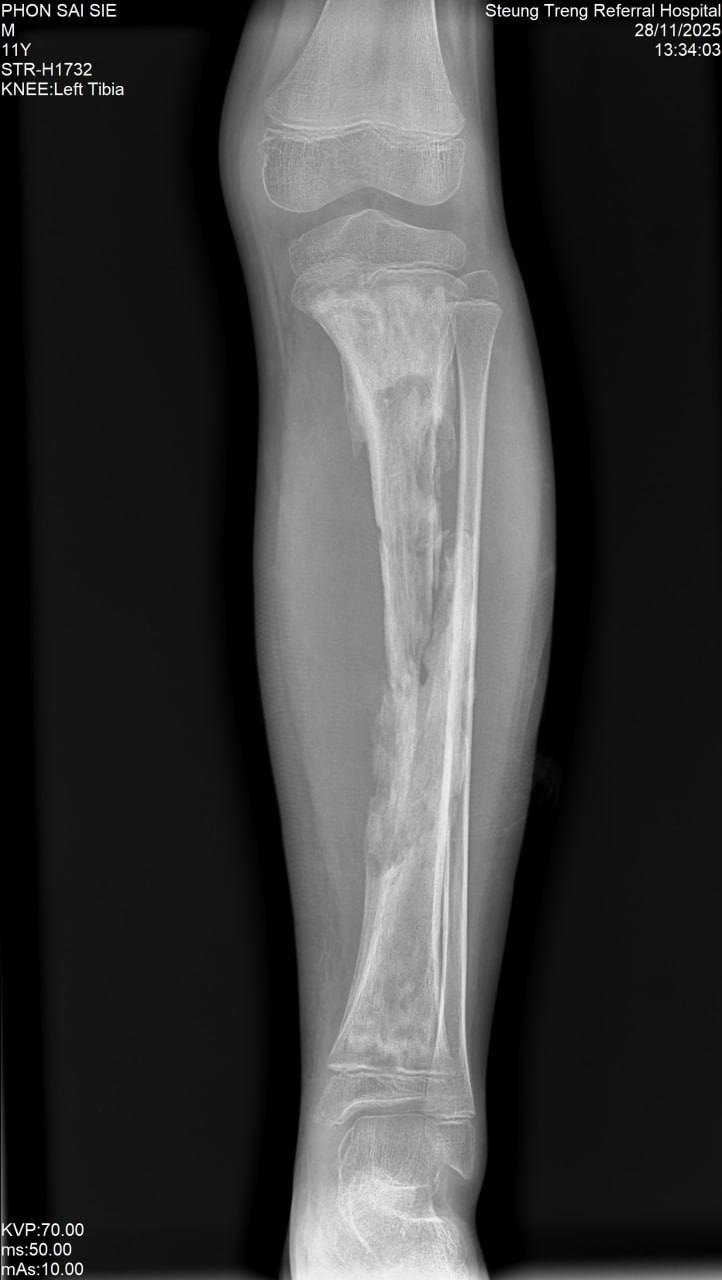

ឯកឧត្តមនាយកមន្ទីរពេទ្យកុមារជាតិនិងឯកឧត្តមប្រធានក្រុមប្រឹក្សាភិបាលនៃសម្ព័ន្ធគ្រូពេទ្យ សសយក បានអនុញ្ញាត្តិអោយលោកវេជ្ជបណ្ឌិត កែវ វណ្ណា នាយករងមន្ទីរពេទ្យកុមារជាតិ បានដឹកនាំក្រុមគ្រូពេទ្យវះកាត់នៃមន្ទីរពេទ្យកុមារជាតិ បំពេញបេសកកម្មមនុស្សធម៍វះកាត់កុមារដែលមានជំងឺ ក្លនលូន ឆែបមាត់ ឆែបក្រអូម ប្រដាប់ភេទខុសប្រក្រតី ដុំពក ពិការអវយវះពីកំណើត ដោយរលាក របួស និងជំងឺត្រចៀក ច្រមុះបំពង់ក នៅមន្ទីរពេទ្យបង្អែកខេត្តស្ទឹងត្រែង ក្រោមការជួយយឧបត្ថម្ភគាំទ្រដោយអភិបាលនៃគណអភិបាលរដ្ឋបាលខេត្ត ស្ទឹងត្រែង បានចំនួន 104 ករណី និងពិនិត្យជំងឺកុមារបាន 353នាក់ ព្រមទាំងបញ្ជូនមកបន្តវះកាត់នៅមន្ទីរពេទ្យកុមារជាតិចំនួន 5នាក់។